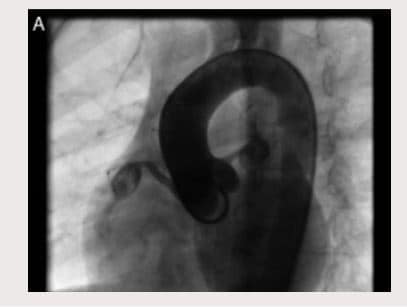

En control ecocardiográfico al mes aún persistían los aneurismas de igual tamaño. Dos meses luego del egreso, presentó fiebre de 39-40? durante dos días, consultó a Urgencias y se administró benzetacil por diagnóstico de amigdalitis. Se hospitalizó para estudio y presentó hipercolesterolemia, trombocitosis y pruebas de función hepática alteradas. El ecocardiograma evidenció aneurisma sacular gigante del tronco coronario izquierdo (13 mm) y dos aneurismas de tamaño moderado a grande (8,2 mm la proximal y 6,6 mm la distal) en la coronaria derecha (Fig. 1A y B). Se inició tratamiento con heparina durante dos meses y posteriormente se trató con warfarina 0,1 mg/kg/día y ácido acetil salicílico 50 mg/día. Se dio de alta con fórmula de ácido acetil-salicílico. Ante la persistencia de aneurismas gigantes se remitió para valoración por Hemodinámica, quienes ordenaron cateterismo cardiaco (Figs. 2A, 2B, 3A y 3B). Se trató con heparina de bajo peso molecular durante un mes y luego con Warfarina en forma permanente.

Figura 2 A. Cateterismo cardíaco en el que se observan dos aneurismas en arteria coronaria derecha ACD (R-right – proximal visible y distal parcialmente visible) y un aneurisma en arteria coronaria izquierda – ACI.

Figura 2 B. Diagrama de cateterismo cardíaco con tres aneurismas coronarios (dos en la arteria coronaria derecha-ACD y uno en la arteria izquierda

– ACI).